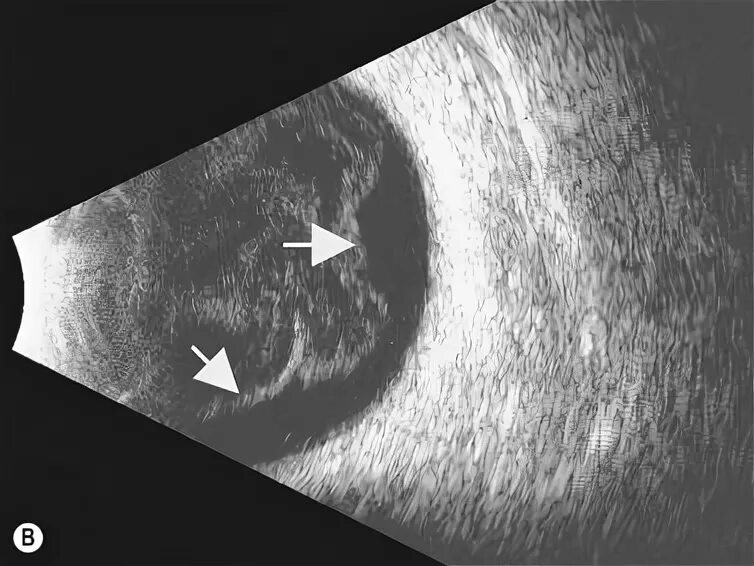

Белое пятно на узи